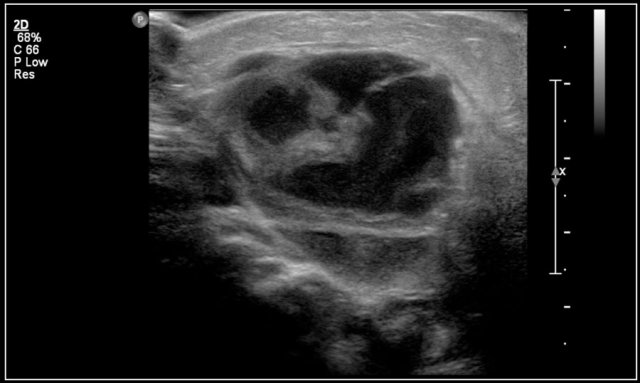

Here another fourteen-year-old boy with a painless swelling in the left neck.

Ultrasound showed several enlarged lymhnodes.

Continue with the MR and PET/CT...

A coronal STIR image shows the pathologic lymph node masses similar to the PET-CT.

The diagnosis was Hodgkin's lymphoma.